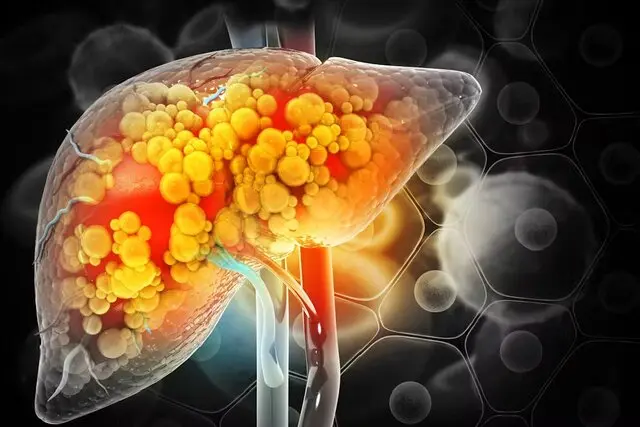

خبرآنلاین: در صورت عدم کنترل کبد چرب، این بیماری میتواند منجر به عوارض جدیتری شود. برخی مکملها از جمله خارمریم، ویتامین E و… هستند که ممکن است به بهبود و کنترل این بیماری کمک کنند..

دکتر فرزاد روشن ضمیر، متخصص تغذیه و رژیم درمانی میگوید: در صورت عدم کنترل کبد چرب، این بیماری میتواند منجر به عوارض جدیتری شود. برخی مکملها از جمله خارمریم، ویتامین E و… هستند که ممکن است به بهبود و کنترل این بیماری کمک کنند..

خارمریم (سیلیمارین)

ترکیب اصلی گیاه خار مریم، سیلیمارین است که یک آنتیاکسیدان قوی محسوب میشود و از سلولهای کبدی در برابر آسیب محافظت میکند. سیلیمارین با کاهش التهاب و دفع سموم، عملکرد طبیعی کبد را بهبود میدهد. پژوهشها نشان دادهاند که این ماده میتواند تا حدودی، آنزیمهای کبدی و نتایج آزمایش خون مرتبط با آسیب کبدی را بهبود دهد.

خارمریم به صورت کپسول، قرص و مایع در دسترس است. دوزهای معمول بین ۲۵۰ تا ۷۵۰ میلیگرم و دو تا سه بار در روز مصرف میشود. عوارض احتمالی شامل نفخ، تهوع، اسهال و گاز معده است. بهتر است این مکمل تحت نظر پزشک مصرف شود.

پروبیوتیکها

پروبیوتیکها به افزایش باکتریهای مفید به ویژه در روده کمک میکنند. سلامت روده نقش مهمی در پیشگیری یا درمان کبد چرب دارد، زیرا باکتریهای مضر میتوانند سطح سموم بدن را افزایش و فشار بر کبد را مضاعف کنند.

پروبیوتیکها با بهبود سلامت روده، کاهش التهاب و تقویت سیستم ایمنی ممکن است به بهبود وضعیت کبد کمک کنند. عوارض رایج شامل نفخ و گاز معده است. انتخاب نوع و مقدار صحیح پروبیوتیک در کنار رژیم غذایی و سبک زندگی مناسب میتواند تأثیر قابلتوجهی بر سلامت کبد داشته باشد.

ویتامین E

ویتامین E یک آنتیاکسیدان قوی که ممکن است التهاب و میزان چربی کبد را بهبود دهد. دوزهای مورد استفاده در مطالعات، بین ۴۰۰ واحد تا ۸۰۰ واحد در روز است که بسیار بیشتر از مقدار توصیه شده برای بزرگسالان سالم است.

حد بالای قابل تحمل برای مصرف روزانه ویتامین E در بزرگسالان ۱۰۰۰ میلیگرم است. مصرف بیش از ۴۰۰ واحد ممکن است خطر خونریزی یا سکته را افزایش دهد. قبل از شروع مصرف مکمل ویتامین E، مشورت با پزشک ضروری است.

زردچوبه (کورکومین)

زردچوبه گیاهی هندی با ماده فعال کورکومین است که خواص آنتیاکسیدانی و ضدالتهاب دارد. این مکمل میتواند سطح آنزیمهای کبدی را کاهش دهد و سطح کلسترول را نیز بهبود بخشد.

اگرچه برخی مطالعات اثربخشی آن را تایید کردهاند، اما نتایج، متناقض است و تحقیقات بیشتری نیاز است. در بسیاری از مطالعات دوز مصرفی بیش از ۱۵۰۰ میلیگرم در روز بوده است. عوارض احتمالی شامل مشکلات گوارشی، سردرد و بثورات پوستی است.

ویتامین D

ویتامین D ممکن است بر عملکرد انسولین، التهاب و واکنشهای ایمنی مؤثر بر سلولهای کبدی تأثیرگذار باشد. تحقیقات نشان دادهاند که بسیاری از بیماران مبتلا به کبد چرب دارای سطح پایین ویتامین D هستند. اگرچه برخی مطالعات از تأثیر مثبت مکمل ویتامین D حمایت کردهاند اما برخی دیگر هیچ تأثیری بر سلامت کبد گزارش نکردهاند. مقدار توصیه شده برای بزرگسالان ۶۰۰ تا ۸۰۰ واحد و حد بالای قابلتحمل آن۴۰۰۰ واحد در روز است.

اسیدهای چرب امگا-۳

اسیدهای چرب امگا-۳ نوعی چربی مفید هستند که به سلامت قلب و کاهش التهاب کمک میکنند. این مکمل در بهبود مقاومت به انسولین، کلسترول بالا و سلامت کبد نقش دارد. برخی مطالعات نشان دادهاند که امگا-۳ آنزیمهای کبدی و میزان چربی کبد را بهبود میبخشد، اما دادهها در مورد اثربخشی کلی آن متناقض هستند و نیاز به تحقیقات بیشتر وجود دارد. میتوان امگا-۳ را از طریق رژیم غذایی یا مکملها دریافت کرد. مقدار توصیه شده روزانه برای بزرگسالان متفاوت است. عوارض احتمالی شامل بوی بد دهان، سوزش معده، سردرد و بوی ماهی است.

برای بهبود کبد چرب، صرفا به مصرف مکملها اکتفا نکنید و در کنار مکملها، ورزش منظم، اصلاح رژیم غذایی، کاهش وزن و محدودیت مصرف الکل باید رعایت شود.